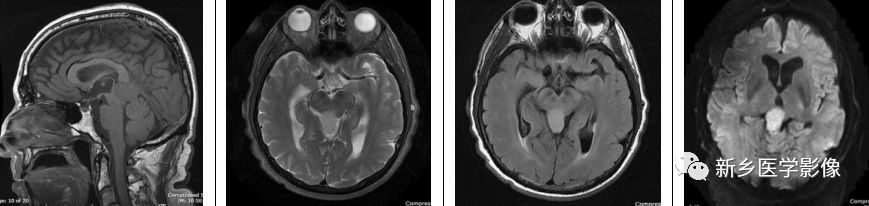

三侧性视网膜母细胞瘤

视网膜母细胞瘤是儿童眼内最常见的恶性肿瘤。该肿瘤通常在幼年期被诊断,通常在2岁以前。Calcification in the globe is seen on CT scans.CT扫描可观察到钙化,组织学检查中,钙化见于95%的视网膜母细胞瘤,这可解释CT上出现高钙化率的原因。三侧性视网膜母细胞瘤一词是指存在双侧视网膜母细胞瘤,伴有相关的中线原发性颅内肿瘤(通常在松果体区域,偶尔在鞍上或鞍旁区域)。约2-11%的双侧视网膜母细胞瘤患者存在这种共存的颅内肿瘤。颅内肿瘤被认为是不同于眼内肿瘤的病变,不是转移灶。通常眼内肿瘤和共存的颅内肿瘤之间通常存在潜伏期,通常约一年。

横断位T2WI示双侧眼球后方异常信号,横断位T1WI+C示异常强化,累及双侧眼球;矢状位T1WI+C示松果体区一强化肿物,符合松果体母细胞瘤,横断位CT示双侧眼球后方见钙化。